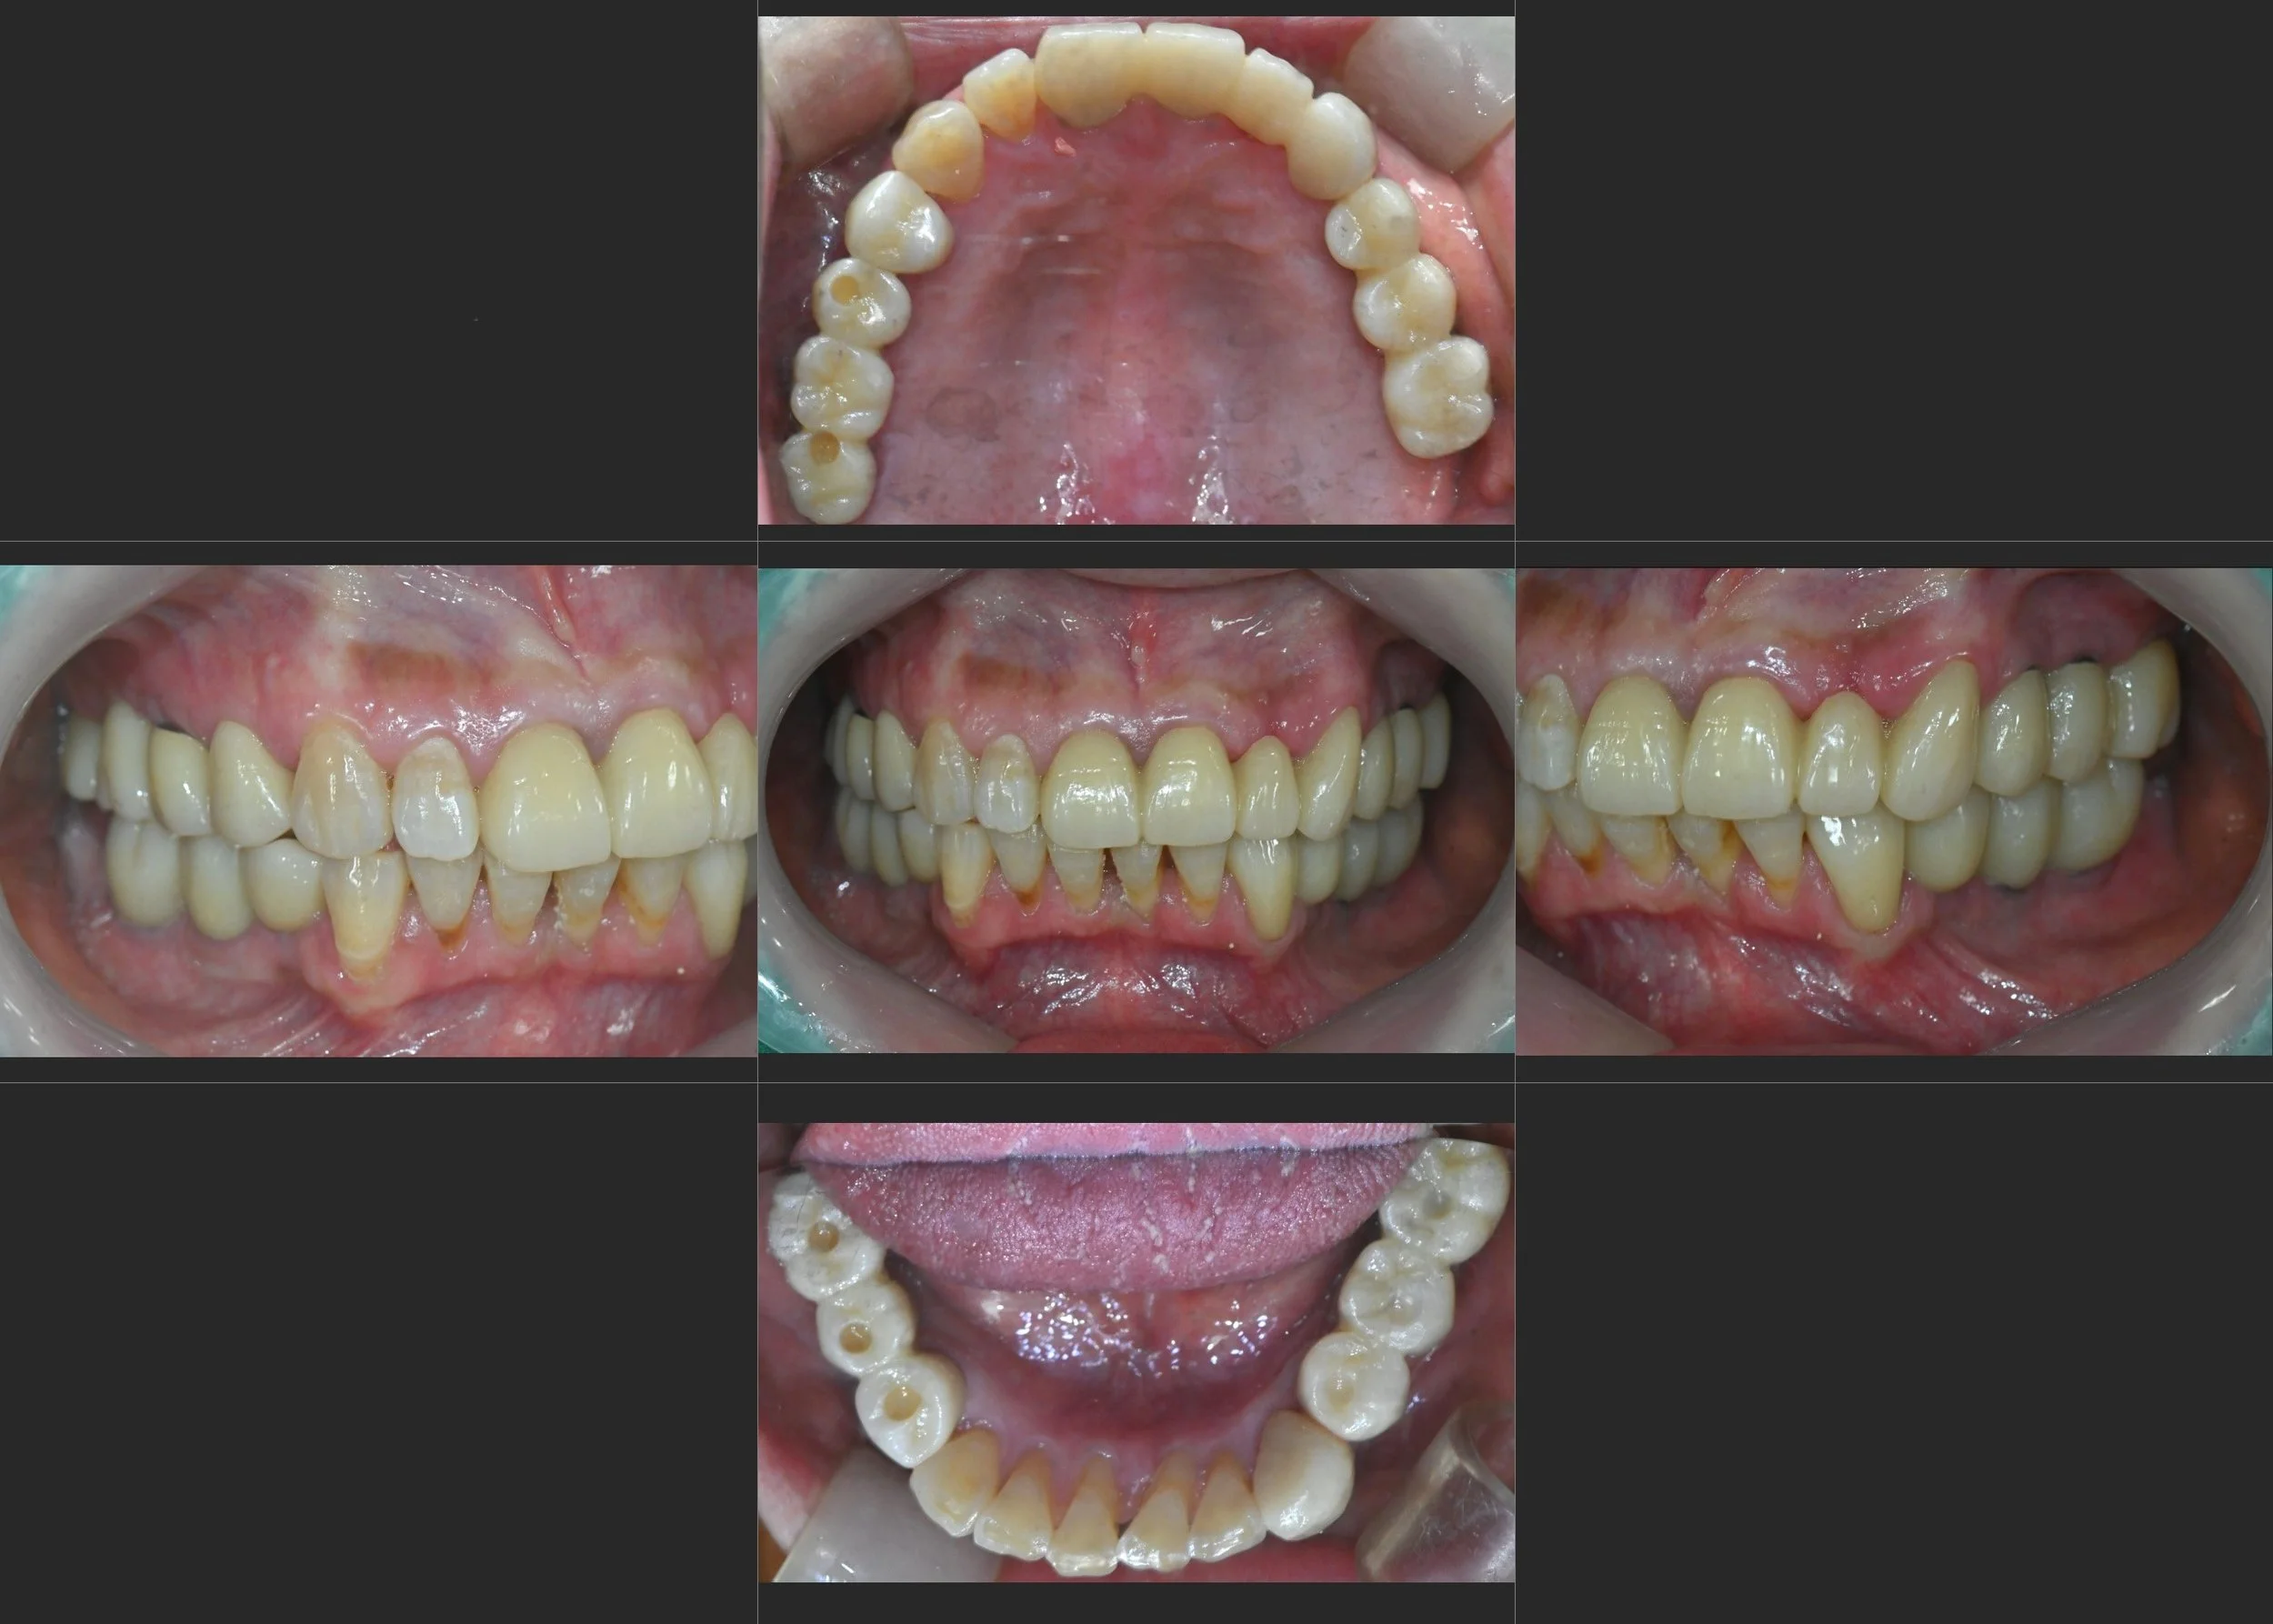

INTRA ORAL - AFTER

4. Final Prosthetic Delivery: Once functional stability was confirmed, the final zirconia bridges and anterior crowns were delivered. The final occlusal scheme provides even force distribution, effectively "unloading" the anterior teeth and ensuring long-term prosthetic durability.

The result is a functional, stable, and highly aesthetic outcome that has profoundly improved the patient's quality of life and social confidence.